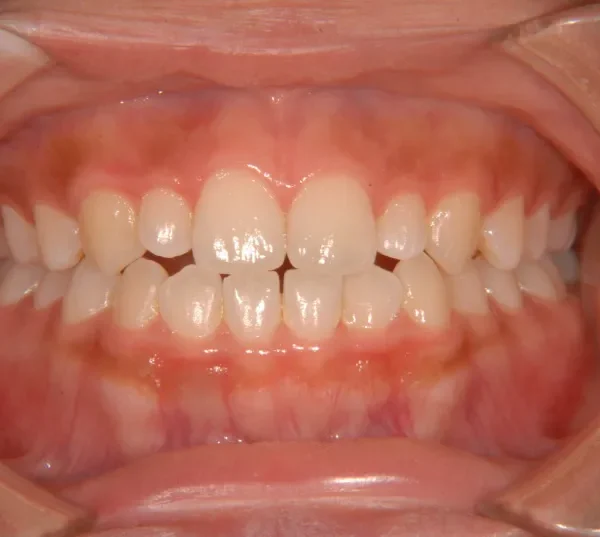

開咬・舌癖・18歳女性

初診時年齢 高校生 (女性) 主訴 開咬 舌癖

状態 前歯で噛めない(開咬/オープンバイト)